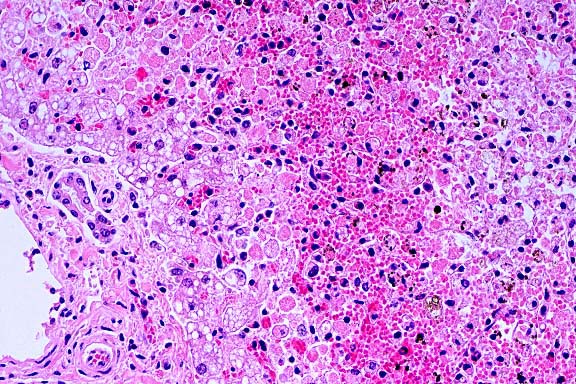

- Case 21-1. Liver. Bile ducts contain neutrophils and

are surrounded by edema. There is degeneration and necrosis of

adjacent hepatocytes.

- Conference Note: Participants identified extensive,

sometimes submassive, hepatic necrosis and neutrophilic portal

inflammation that multifocally filled bile ducts and disrupted

the limiting plate. Viable hepatocytes were present among individually

dissociated and necrotic hepatocytes. In addition to necrosis

of the tubular epithelium in the kidney, tubular regeneration

and casts were observed.